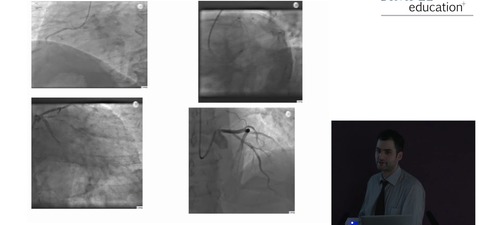

Yousif Ahmad discusses the case of 67-year old man, (ex-smoker, hyperlipidaemia) when incidental LAD stenosis discovered on CT during a routine health check.